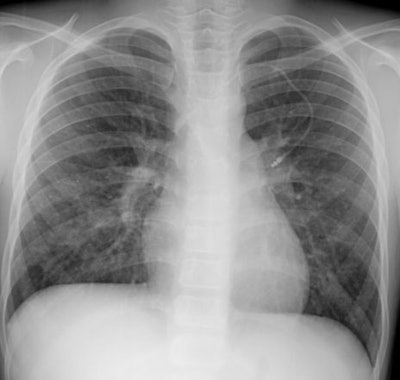

LymphoproliferativeLymph > LIP > Images > Case1Scott WilliamsApr 2, 2002 Lymphocytic Interstitial Pneumonitis: This is a film on an 11 year old HIV positive male. The CXR reveals a diffuse, symmetric nodular pattern. The nodules were noted to wax and wane in size and number over time. Latest in LymphoproliferativeLymph > Nodular lymphoid hyperplasiaFebruary 12, 2014SponsoredClinically Meaningful AI Detection of Interval CancersNovember 1, 2025Lymph > Pulmonary lymphangiectasisJanuary 3, 2010Lymph > GeneralApril 2, 2002Related StoriesLymphoproliferativeLymph > Lymphoma > HodgkinsLymphoproliferativeLymph > Lymphoma > Non-Hodgkins > Images > Nonhodgkins > Case1LymphoproliferativeLymph > Lymphoma > Non-Hodgkins > Images > Nonhodgkins > Case2Sponsor ContentClinically Meaningful AI Detection of Interval Cancers